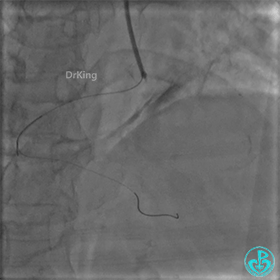

PL远端血管周围似乎有片状造影剂滞留。

经微导管PL分支造影,该如何解读这个经微导管造影结果?

经指引导管造影。

经微导管造影。